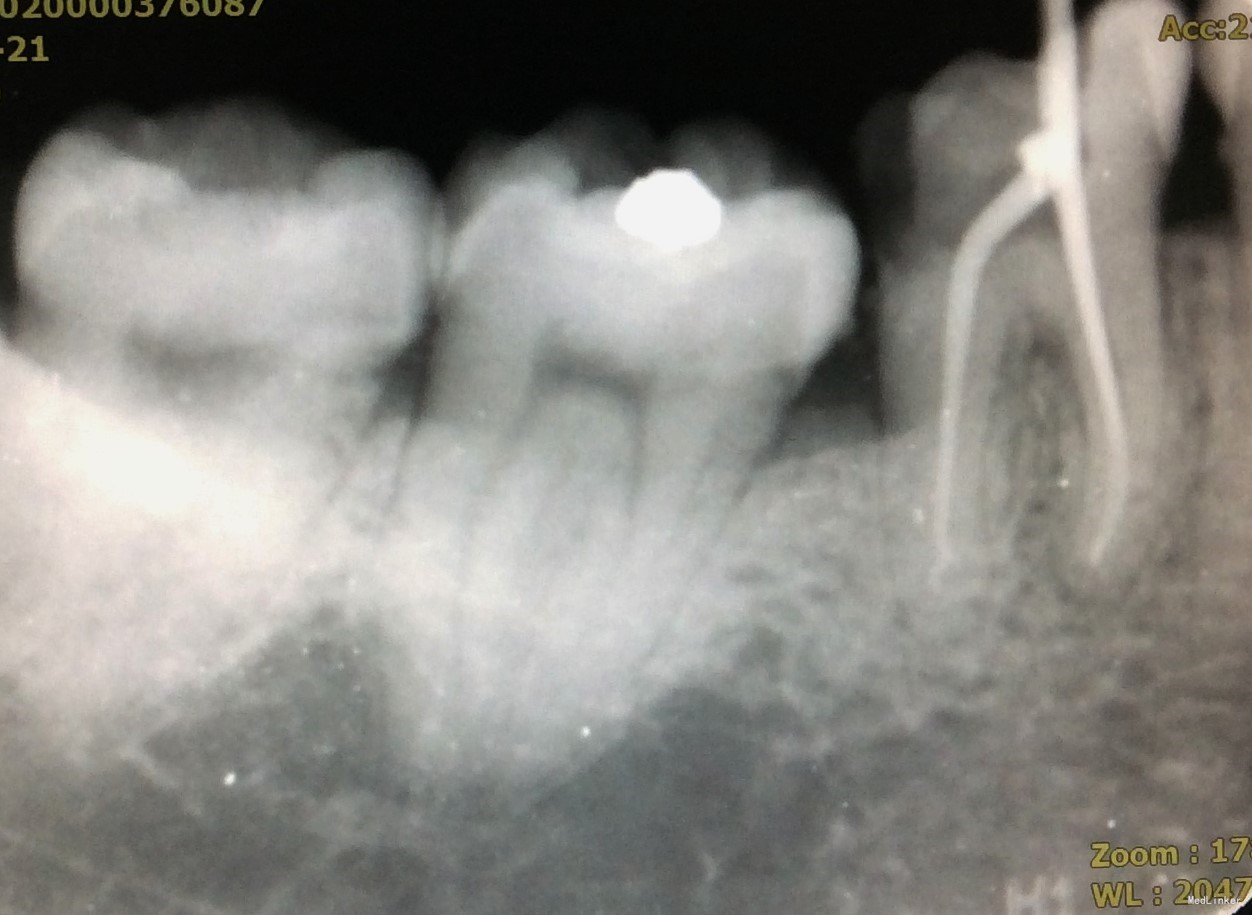

二次复诊:46牙上橡皮障,去暂封,荡洗根管,次氯酸钠冲洗,干燥根管,AH糊剂加大椎度牙胶充填根尖段根管,热牙胶封闭上段根管;远中根预备纤维桩道,粘接纤维桩,行牙体树脂粘接修复。建议观察1周,若无明显不适,至修复可行冠修复。建议牙周科会诊46牙。

3、AH糊剂调拌的状态可能会影响根充的质量。本病例中,近中根、远中根均有不均匀高密度影,为相对较稠的AH糊剂。根充时应注意AH糊剂是否已固化,且应在根管中上下提拉主牙胶尖数次以使糊剂充分到达根尖处,且均匀分布于根管内。

4、若远中根根管粗大,可充填副尖以更好地封闭根尖段。

5、从该病例中可发现,远中根根尖孔开口应位于远中,不在根尖。因根尖孔的解剖位置差异大,根管治疗应充分利用根测仪测量准确的长度,不能仅凭X线片来判断。